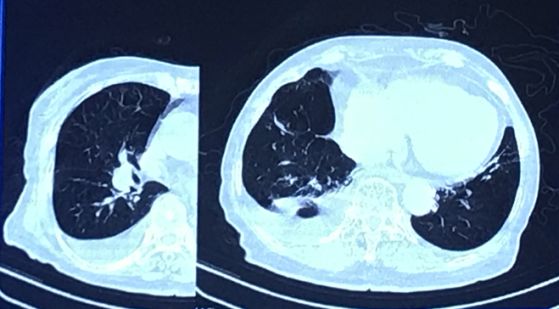

王建安院长分享了两个病例。病例一:患者女,74岁。劳力性呼吸困难10年,阵发性夜间呼吸困难,NYHA Ⅳ级。PMH提示为COPD,2型呼吸衰竭,肺动脉高压。STS风险评分为8.68%。肺功能测试结果提示不耐受。PO2 62.4 mm Hg,PCO2 60.3 mm Hg,pH 7.399,BE 9.8 mmol/L,乳酸 1.2 mmol/L,影像学评估如Figure 2所示。

Figure 2

影像学评估